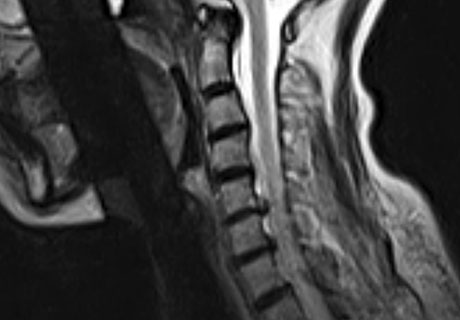

MRI로 본 환자 치료사례 (치료기간-입원치료 3주, 외래치료 1개월 / ABCDE 치료법)

모커리는 파열된 목디스크도 흡수될 수 있도록 도와주는 치료를 합니다.

※ After 사진은 6개월 후 촬영된 모습으로, 파열된 디스크가 깨끗하게 흡수된 것을 확인할 수 있습니다.